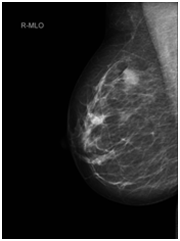

Staging CT chest & abdomen, showed bilateral lung nodules and numerous subcutaneous nodules, the largest seen in the umbilical area (Figure 4). Histology of the right breast biopsy reported staining for Melan-A & HMB45 is positive (Figures 5A‒5D). No staining for Cam5.2, ER, PR, CK7 and CK20. Ki67 is 10%. Appearances and immuno-profile are consistent with metastatic malignant melanoma. Due to disease dissemination, the patient has been referred to palliative oncological treatment.

Figure 5(A) x2 magnification: normal breast lobules at 7’oclock, sheets of melanoma at the centre and necrosis with melanin pigment at 1’oclock.

Figure 5(B) x4 magnification: normal breast lobules at 7’oclock, sheets of melanoma at the centre and necrosis with melanin pigment at 1’oclock.